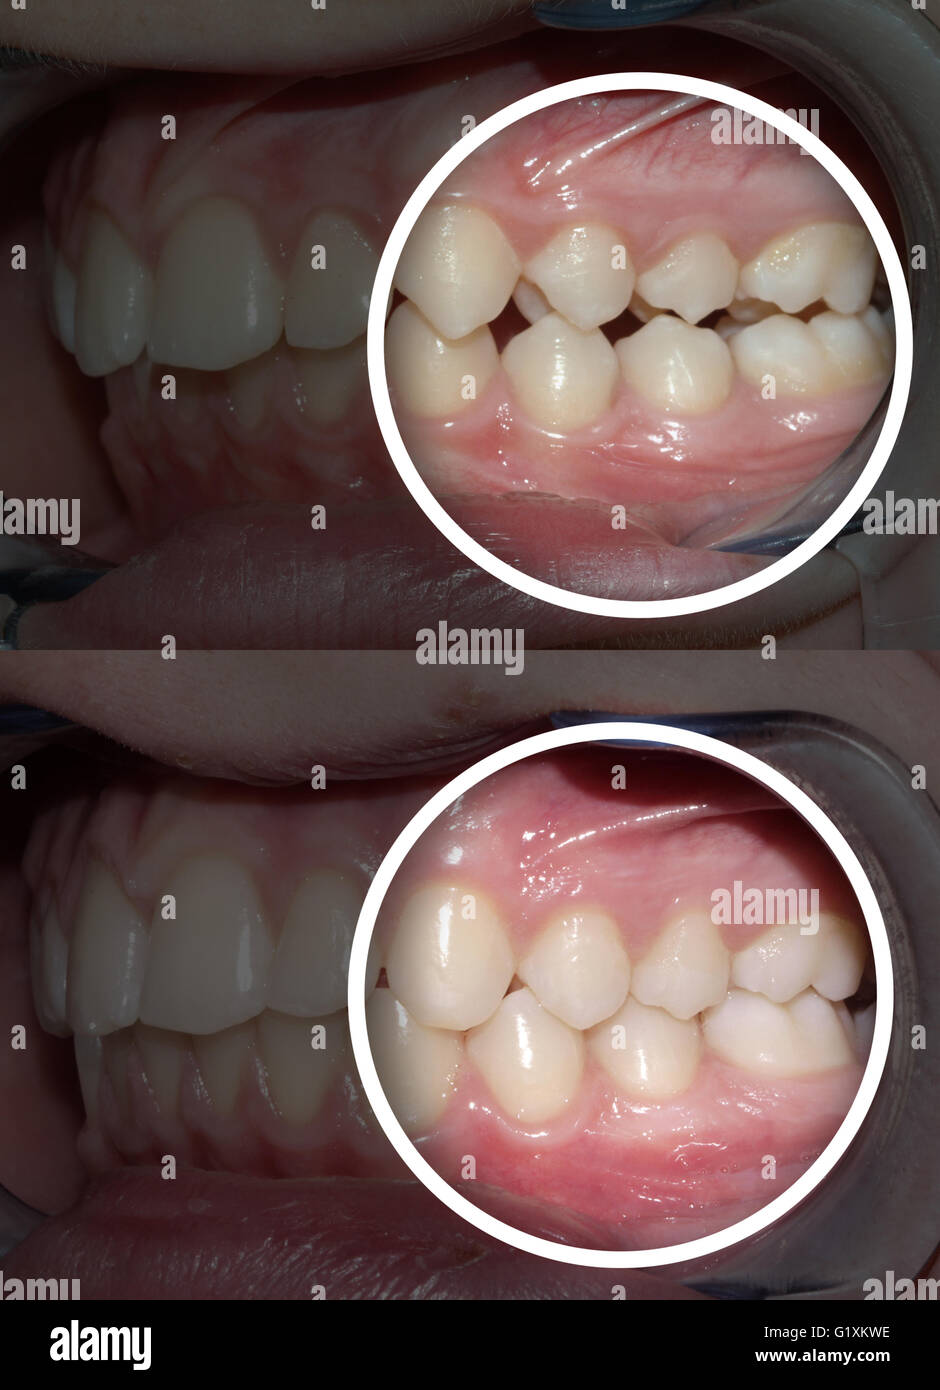

Source: www.alamy.de

Caninusfehlstellung beim hund (02.09.2005) die 8 monate alte border colliehündin vanilla” wurde uns mit einem engstand beider unterkiefereckzähne vorgestellt, wodurch mesial der. Die zahnspange beim hund wird unter narkose eingesetzt. Ein unterer fangzahn wächst direkt ins oberkiefer.

Malocclusion Stockfotos und bilder Kaufen Alamy

Eine besondere zahnfehlstellung ist beim hund allerdings recht häufig und muss meist behandelt werden. Eine zahnfehlstellung bezeichnet jegliche stellung eines zahnes oder mehrerer zähne außerhalb der idealen zahnbogenform des oberkiefers oder unterkiefers. Das gebiss des hundes ist ausdrucksmittel, waffe, jagdinstrument und fresswerkzeug in einem.

Underbite Stockfotos & Underbite Bilder Alamy